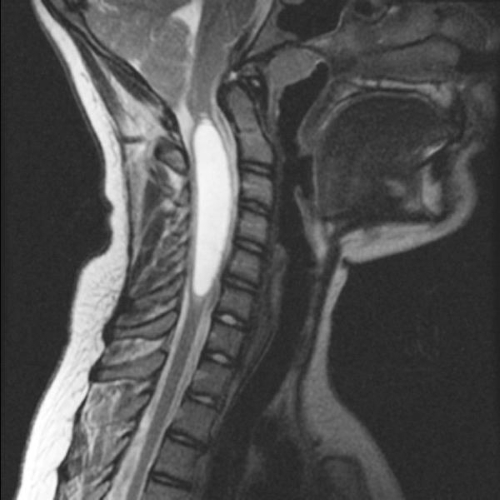

Гидромиелия грудного и шейного отделов позвоночника

Гидромиелия — патология, которую связывают с повреждениями спинномозгового канала. Обычно болезнь поражает шейный отдел позвоночника, но может возникать и в области грудины. При обнаружении недуга следует сразу же приступать к терапии.

Каждый пациент может по-разному ощущать патологию. Чтобы установить точный диагноз, следует провести МРТ спинного мозга. Определить заболевание можно с помощью рентгенографии.